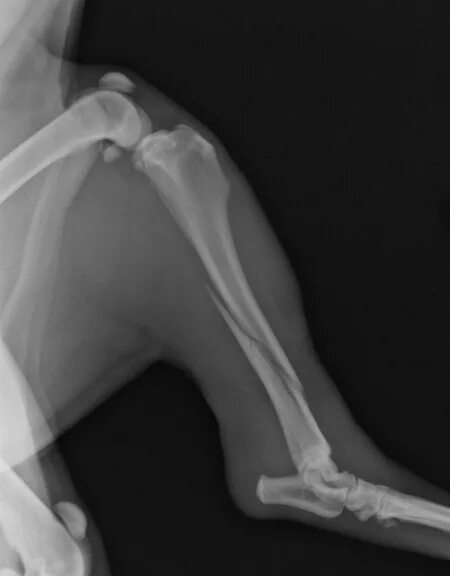

Снимок перелома со смещением